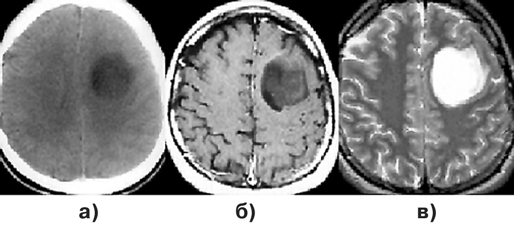

Для доброкачественных диффузных астроцитом при КТ наиболее характерна зона понижения плотности, не имеющая четких границ с окружающим мозговым веществом (рис. 1а, г). Внутривенное введение контрастного вещества обычно не приводит к повышению рентгеновской плотности очага. Разрешающая способность КТ недостаточна для идентификации границ опухоли, особенно изоплотностной по отношению к мозговому веществу.

МРТ — более точный метод визуализации астроцитом. Доброкачественные астроцитомы представляются изо— или гипоинтенсивными на Т1-взвешенных изображениях (рис. 1б, д). В режиме Т2, наиболее информативном при данной патологии, эти опухоли могут выглядеть как сравнительно хорошо отграниченная зона гомогенно повышенного сигнала (рис. 1в, е). “Масс-эффект” выражен, как правило, незначительно, контраст накапливается редко. Так как эти опухоли обычно диагностируются только на стадии выраженных клинических проявлений, для них типично поражение одновременно нескольких долей мозга. Перифокальный отек не характерен.

Рисунок 1. Астроцитомы:

а — астроцитома левой заднелобной области (КТ с контрастным усилением); б — астроцитома левой заднелобной области (МРТ, Т1-взвешенные изображения); в — астроцитома левой заднелобной области (МРТ, Т2-взвешенные изображения); г — фибриллярная астроцитома правой лобно-височной области (КТ с контрастным усилением); д — фибриллярная астроцитома правой лобно-височной области (МРТ, Т1-взвешенные изображения); е — фибриллярная астроцитома правой лобно-височной области (МРТ, Т2-взвешенные изображения)

Инфильтративно растущие астроцитомы могут распространяться и за пределы видимой на Т2-взвешенных томограммах зоны изменения сигнала. Для них характерно поражение как белого, так и серого вещества мозга. Это приводит к стиранию обычно видимых на МРТ границ между белым и серым веществом мозга. Извилины в этих случаях выглядят утолщенными, определяется “масс-эффект” в виде смещения окружающих структур мозга. Опухоли большой распространенности сопровождаются дислокацией мозга с развитием синдромов вклинения. Большинство доброкачественных астроцитом — сóлидные новообразования.